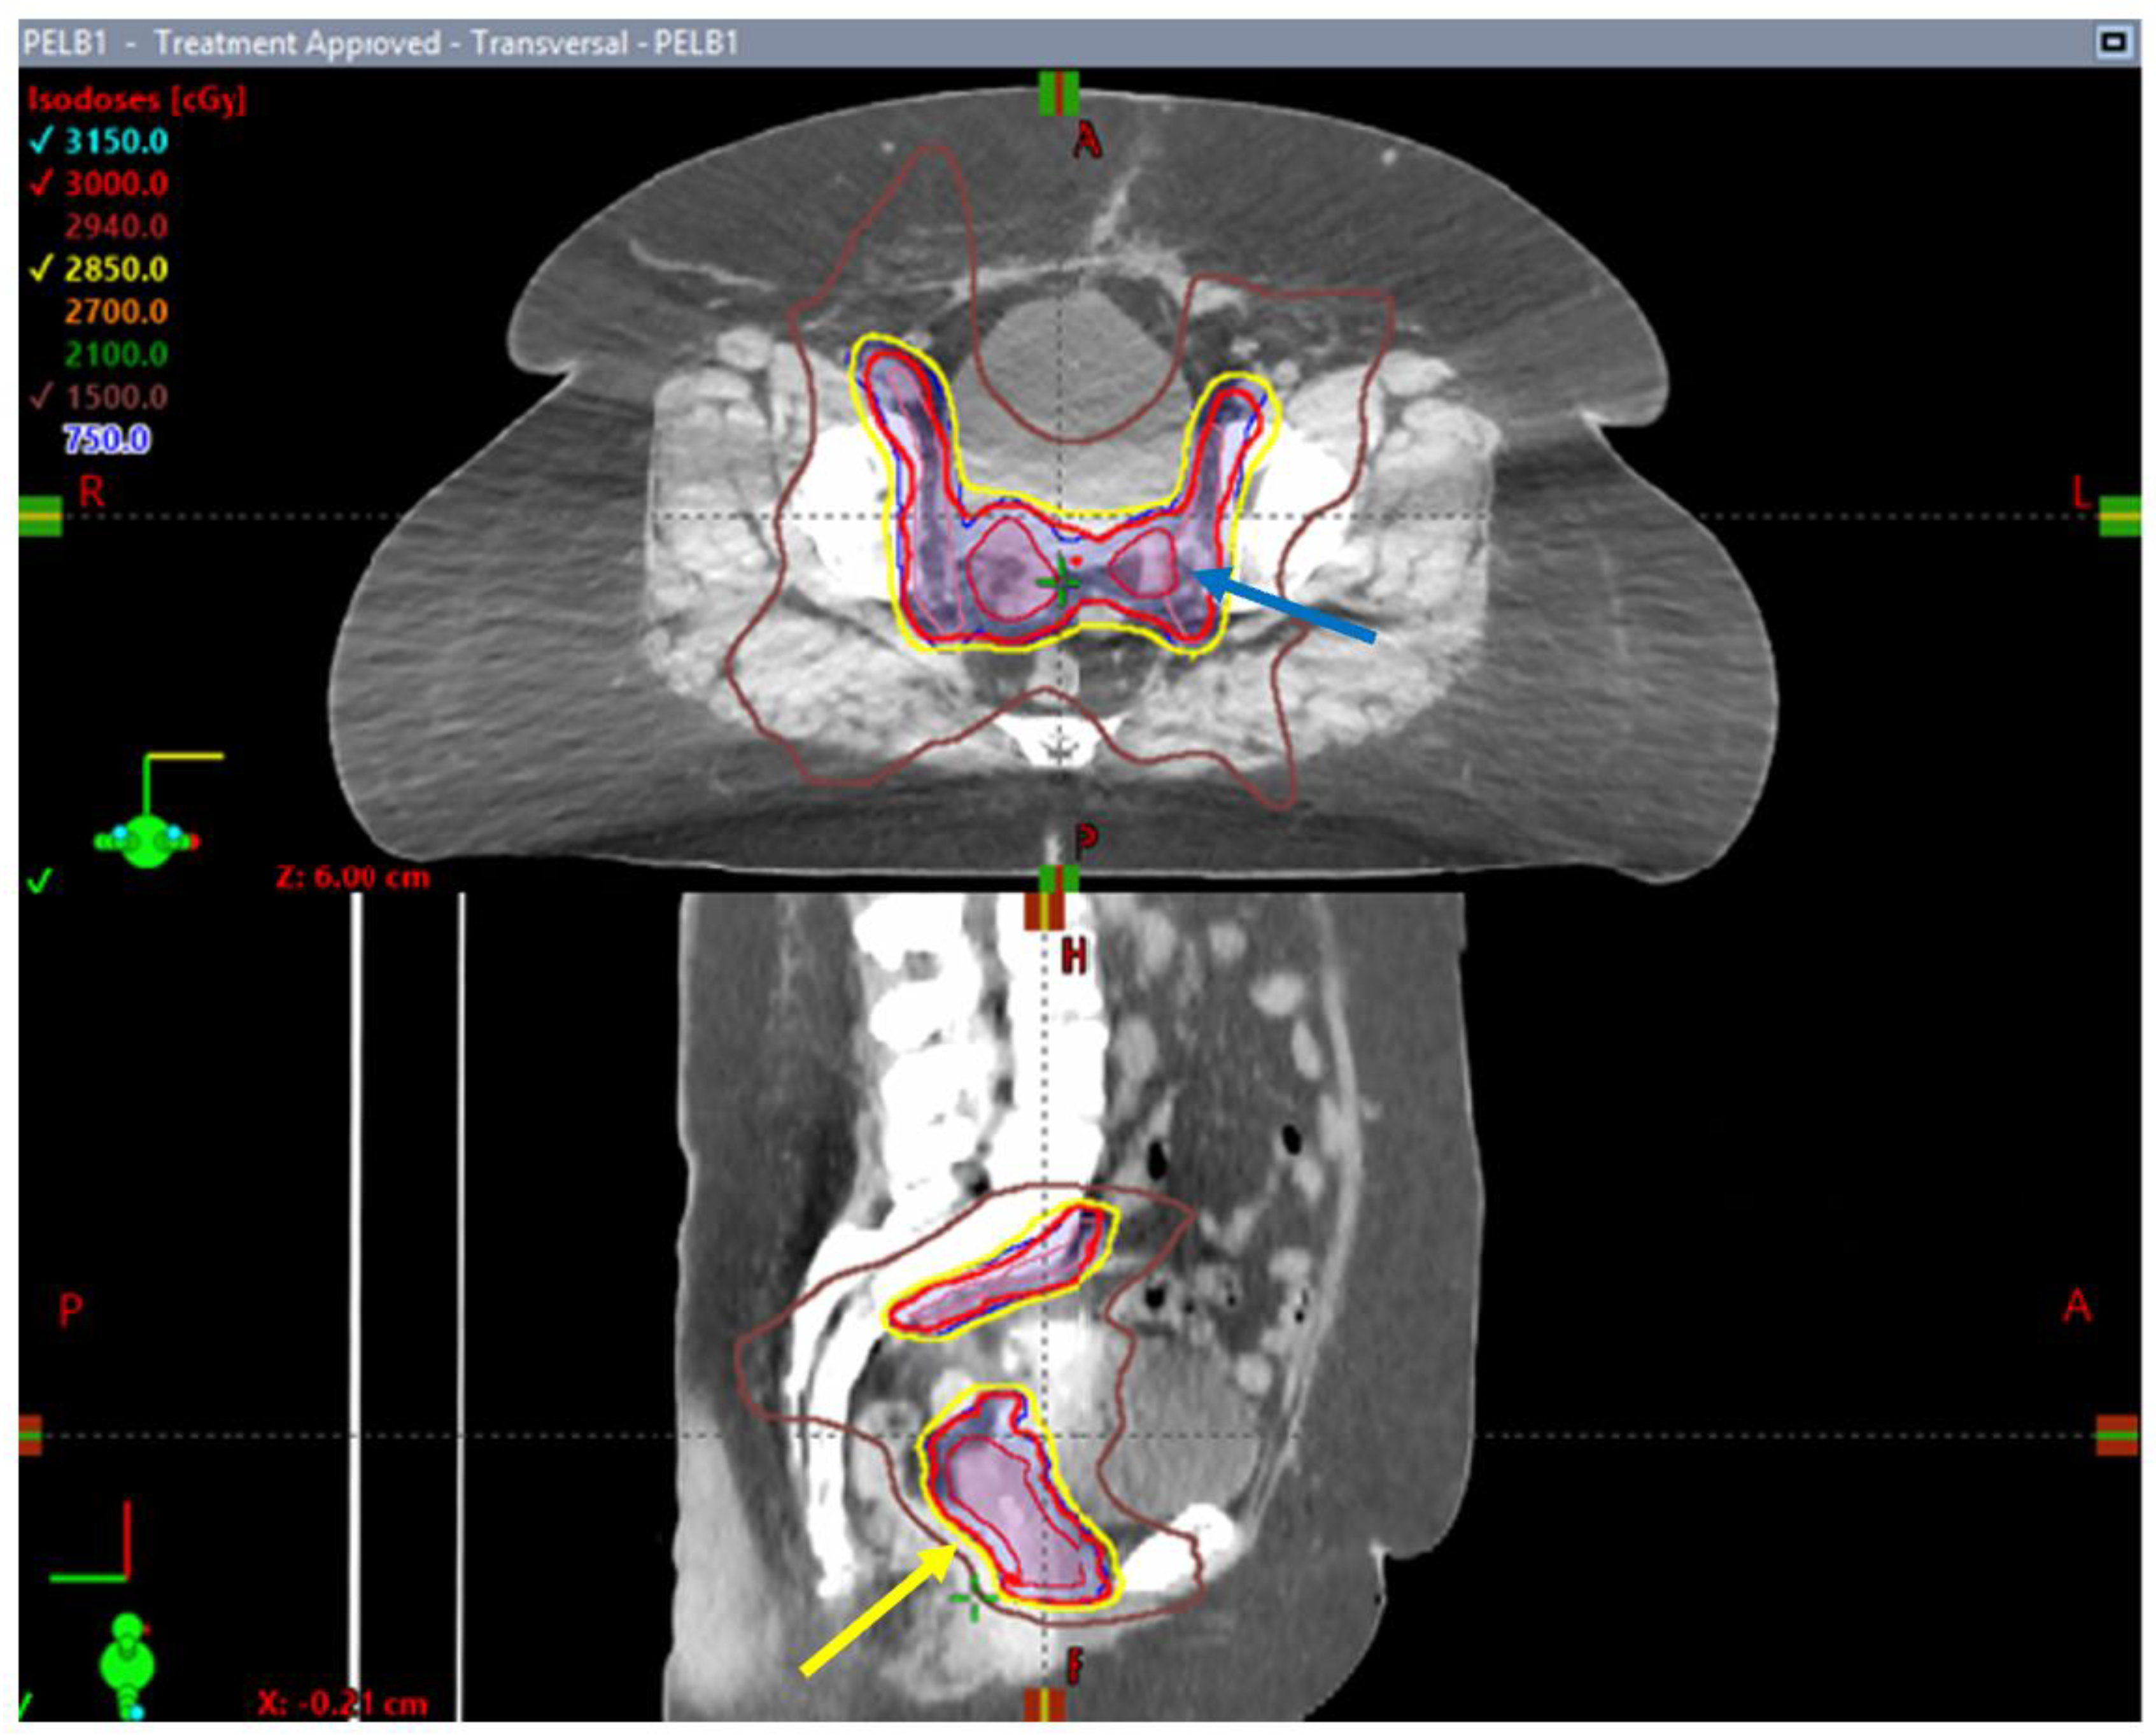

- Leung, E.; Gladwish, A.P.; Davidson, M.; Taggar, A.; Velker, V.; Barnes, E.; Mendez, L.; Donovan, E.; Gien, L.T.; Covens, A.; et al. Quality-of-Life Outcomes and Toxic Effects Among Patients with Cancers of the Uterus Treated with Stereotactic Pelvic Adjuvant Radiation Therapy: The SPARTACUS Phase 1/2 Nonrandomized Controlled Trial. JAMA Oncol. 2022, 8, 853. [Google Scholar] [CrossRef] [PubMed]